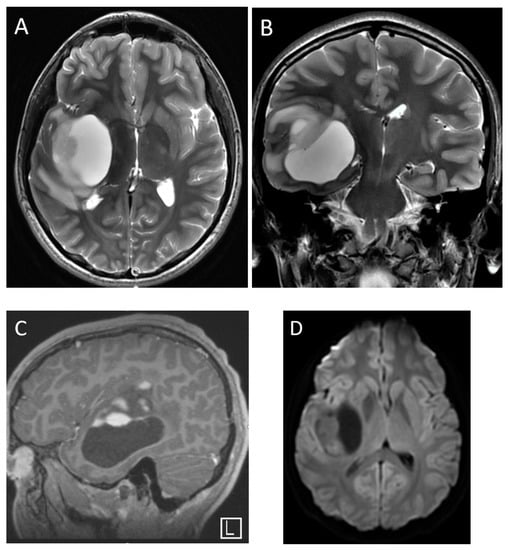

| Medulloblastoma | Exclusively posterior fossa Most commonly in fourth ventricle/cerebellar vermis (non-WNT, non-SHH, or WNT), can involve cerebellopontine angle (WNT) or cerebellar hemispheres with extra-axial extension (SHH) | Diffusion restricting Variable enhancement Cystic/necrotic change may be present Calcifications uncommon Taurine peak characteristic |

| Atypical teratoid/rhabdoid tumor | Posterior fossa (slightly more common) or cerebral hemispheres May be extra-axial | Diffusion restricting Enhancement usually present More heterogenous than medulloblastomas, with cysts/necrosis, calcification, and hemorrhage |